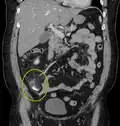

-

Appendicolith as seen on CT -